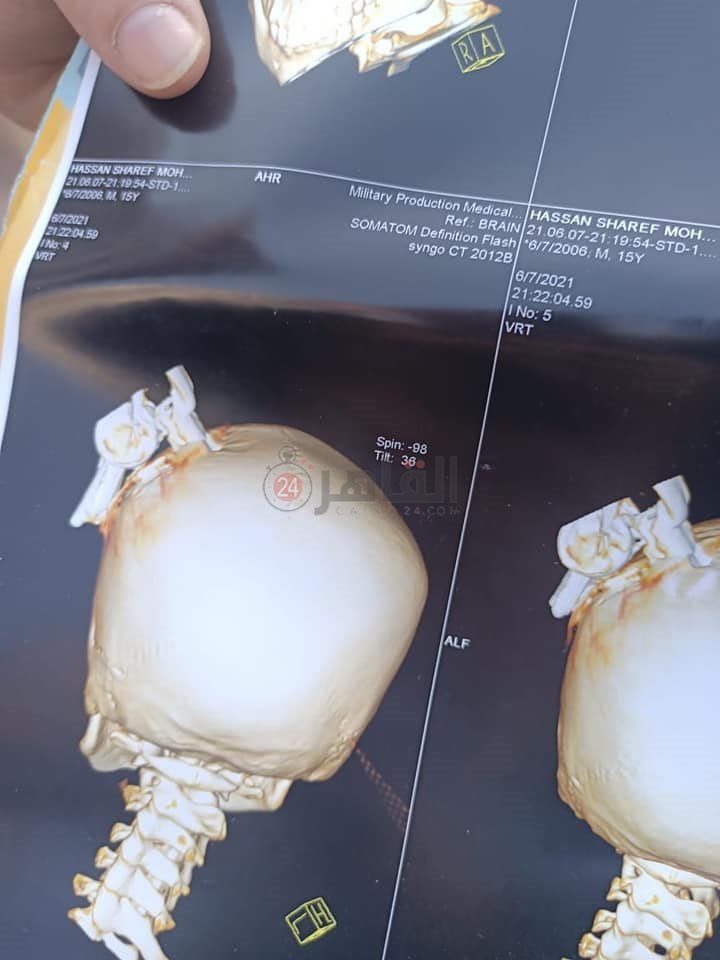

الطفل المصاب

نشر الإعلامي محمد نشأت صورًا لطفل يدعى "حسن" من داخل المستشفى على حسابه بموقع «فيس بوك»، كان زميله ويدعى "معاذ" الذي شارك من قبل في برنامج ذا فويس كيدز قد اعتدى عليه وضربه بمفتاح سيارة في رأسه، ما أدى إلى كسر في الجمجمة، دخل على إثرها في غيبوبة، وتم نقله إلى المستشفى، حيث استغرق 12 ساعة داخل غرفة العمليات لإسعافه.

ووفقًا للتحريات فإن الطفل المعتدي استفز زميله المصاب قبل الواقعة بدقائق واعتدى عليه، وأدخل مفتاح السيارة بالكامل في رأسه قبل أن يتم إنقاذ حياته.